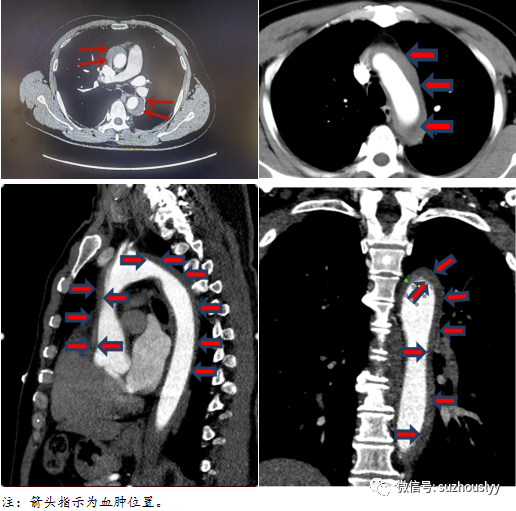

患者,男性,59岁。2021年12月突发胸背部疼痛,伴有恶心呕吐,本以为休息一会就能缓解,但仅几个小时内病情加重,胸背部持续刀割样疼痛,大汗淋漓,难以忍受,急诊120送入我院。查胸主动脉CTA提示:升主动脉、主动脉弓、头臂干、右侧颈内动脉、降主动脉全程广泛壁间血肿,但未见明显破口。该患者病情危重,随时可能进一步进展恶化,汇报医务科、院领导后,启动现场紧急院内会诊,张学勤主任及时到场现场制定诊疗方案,病人病情很快稳定。张主任综合各项检查结果和病人整体状况,因急诊手术的风险很高,先行采取保守治疗,待病情相对稳定后再进一步确定手术时机患者获益可能更大,同时积极准备手术事宜,完善各项术前准备,以应对患者的病情变化。患者家属本来已经有放弃治疗念头,又重新燃起了希望,同意并积极配合诊疗方案。

随后,患者收治于我院心脏大血管外科,张主任组织全院会诊开展病例讨论、制定治疗计划,评估病程中可能发生的风险及并发症,演练多阶段治疗细则,同时上报医务科开放绿色通道,联系多科室通力协作,提供技术及设备支持,保障患者围手术期安全。拟定行体外循环下深低温选择性脑灌注下半身停循环的“孙氏手术”,即:应用人工血管替换升主动脉+主动脉弓,降主动脉内植入象鼻支架血管,主动脉弓的三分支重建。根据患者术中探查情况,如果患者血管条件良好,可以简化手术简化手术方案为升主动脉和主动脉弓半弓人工血管置换可在保证类似的远期效果的同时有效降低手术并发症和死亡率,同时也为患者节省三分之一的手术费用。